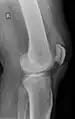

An x-ray demonstrating quadriceps tendon rupture. Note the abnormal angle of the patella and soft-tissue swelling marked by the arrow.